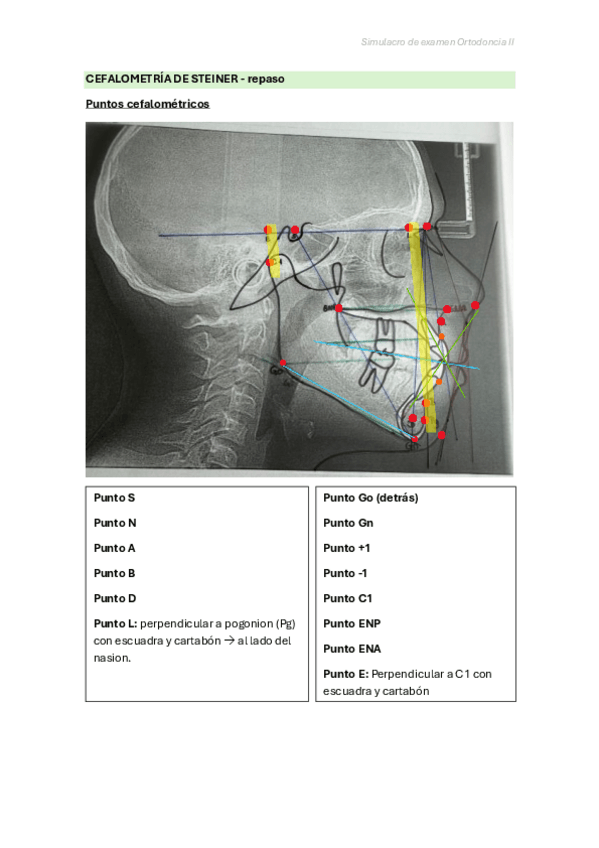

Repaso rápido para cefalometría de steiner